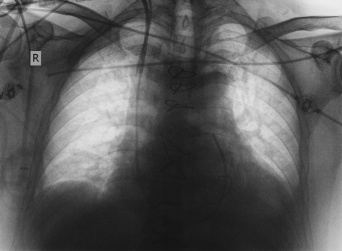

「科学の名のもとに。自分の静脈にカテーテルを突っ込みノーベル賞を受賞した医師「ヴェルナー・フォルスマン」の物語」のページです。デイリーニュースオンラインは、社会などの最新ニュースを毎日配信しています。